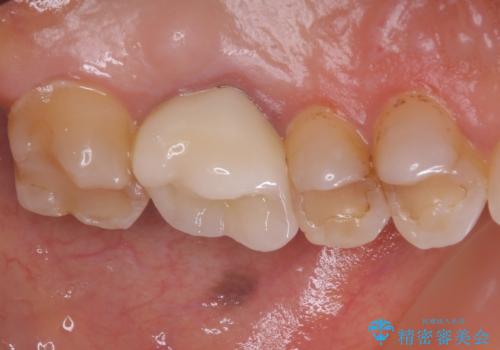

- 奥歯に装着したクラウンの周りに汚れが溜まりやすいとのことで来院された患者様です。

既に装着されているクラウンの質は決して悪いものではありませんでしたが、患者様自身が非常に気にしていたため、作り替えの治療を行うこととしました。

根管治療が必要と思えるような所見も認められませんでしたが、一緒に行いたいとの希望があったため、根管治療を行った上で補綴治療を行うこととしました。

クラウン装着後は、特にものが挟まる感覚もなく、快適に過ごすことができるようになりました。